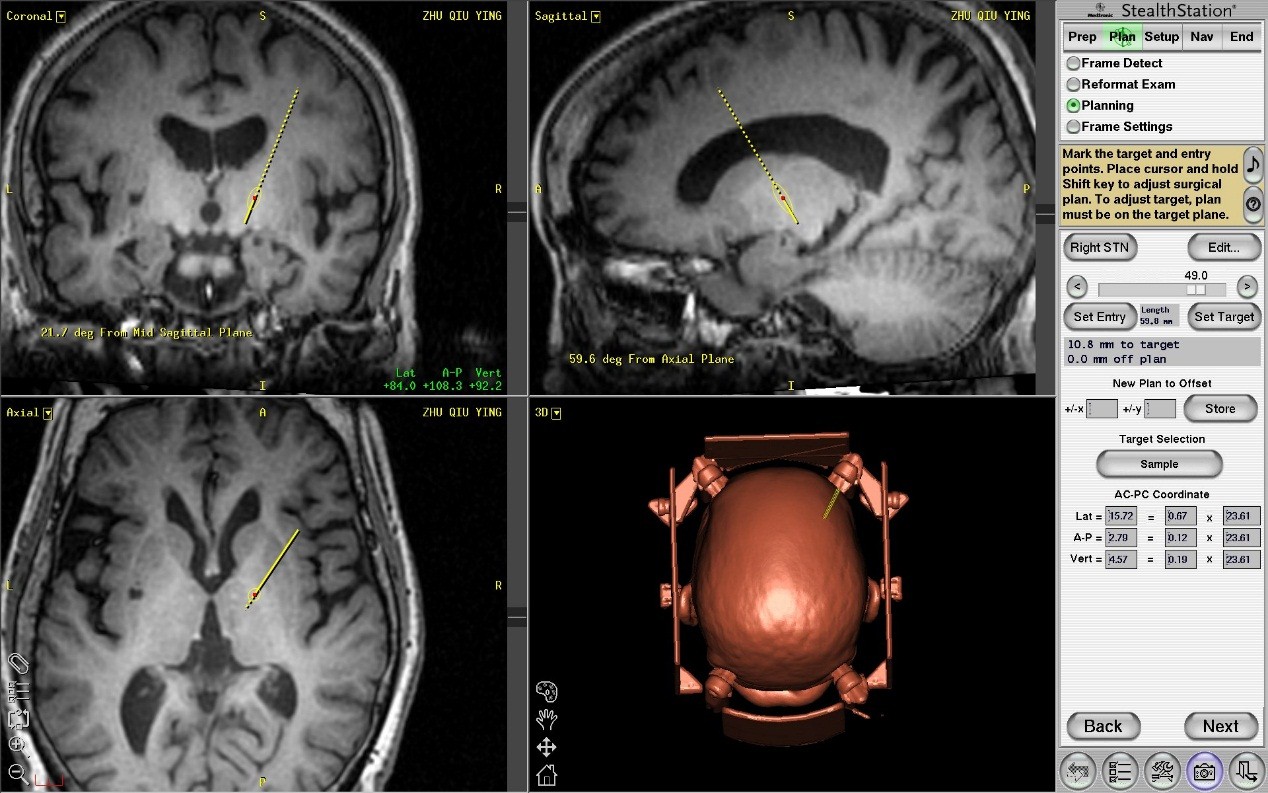

2名患者十余年来辗转国内知名医院就诊,均未取得满意的治疗结果,饱受疾病摧残,慕名来我院求医。王劲接诊患者后,耐心、细致地向病人及家属讲解了手术治疗方式及可能出现的手术风险。患者入院后,王贵怀亲自指导神经外科医师董生为患者进行了详细的神经功能评估、检查,并使用目前最先进的影像导航系统美敦力Stealth station 7为患者制定个体化的手术入路,确定了脑起搏器靶点位置(图1 所示)。

图1 术前规划手术入路,计算靶点